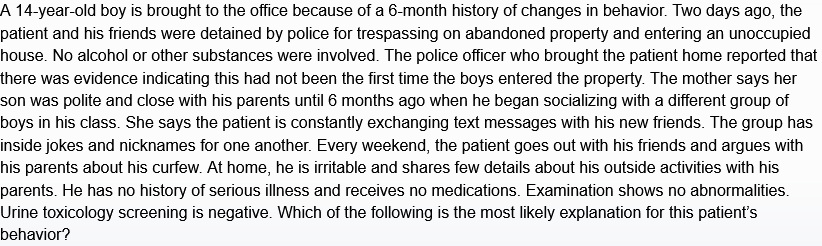

peds w/ periumbilicul → rlq pain, mucus stools, fever

infectious ileocolitis

campylobacter